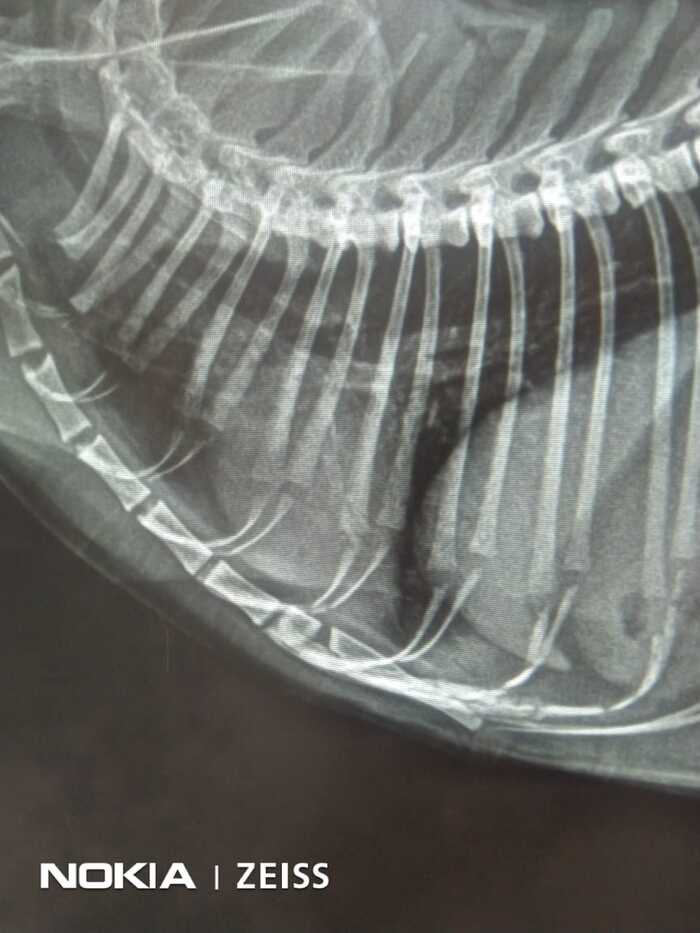

Помимо этого провели исследования ЭХО, УЗИ, ЭКГ, и контрольные анализы крови. Все в пределах нормы. Инфекционных и вирусных заболеваний нет.

К сожалению, сегодня опять не смогли сделать МРТ. Но нет худа без добра. Нашли клинику в которой сразу сделают МРТ двух отделов, шейного и головы, и КТ грудной клетки. И обойдется это дешевле, чем в той клинике, где планировали. Хотя сумма всё равно впечатляет. Все процедуры обойдутся в 28к рублей.